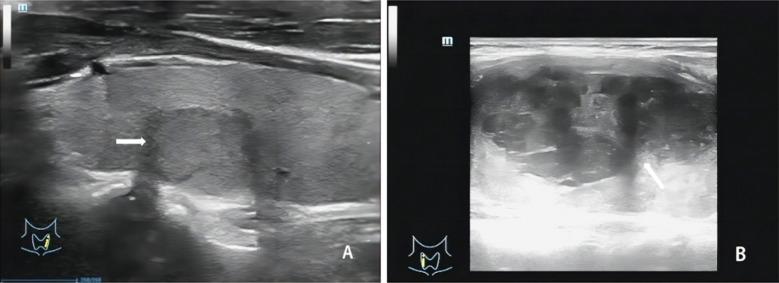

甲状腺乳头状癌超声检查参数与病理特征的相关性

The correlation between the ultrasound examination parameters and the pathological characteristics of papillary thyroid carcinomas.

To evaluate the correlation between ultrasound (US) examination parameters and pathological characteristics of papillary thyroid carcinomas (PTC).

METHODS

A retrospective analysis was conducted using clinical data from 89 patients with PTC (malignant group) and 89 patients with benign thyroid nodules (benign group) who underwent US at Chengdu Shuangliu Hospital of Traditional Chinese Medicine between February 2021 to February 2023. The correlation between ultrasound parameters and pathological features of PTC was analyzed.

RESULTS

Ultrasound parameters in the malignant group were significantly different from those in the benign group (<0.05). Peak systolic blood flow velocity (PSV), pulsation index (PI), and resistance index (RI) were significantly higher in patients with malignant lymph node metastasis (LNM) and stage III-IV PTC. In contrast, peak intensity (Peak), mean transit time (MTT), time to peak (TTP), and area under curve (AUC) were significantly lower than those in patients without LNM and stage I-II (<0.05). Spearman's analysis revealed significant correlations between ultrasound parameters, LNM, disease staging, and gene mutations (). Of the 89 PTC patients, 27 had disease recurrence, and five died during the follow-up. The poor prognosis group had significantly higher PSV, PI, and RI and lower Peak, MTT, TTP, and AUC compared to the good prognosis group (<0.05).

CONCLUSIONS

Ultrasound is a valuable tool for diagnosing and evaluating papillary thyroid carcinoma (PTC). It shows strong correlations between ultrasound parameters and pathological features, including lymph node metastasis and disease staging, aiding early diagnosis and prognosis prediction.